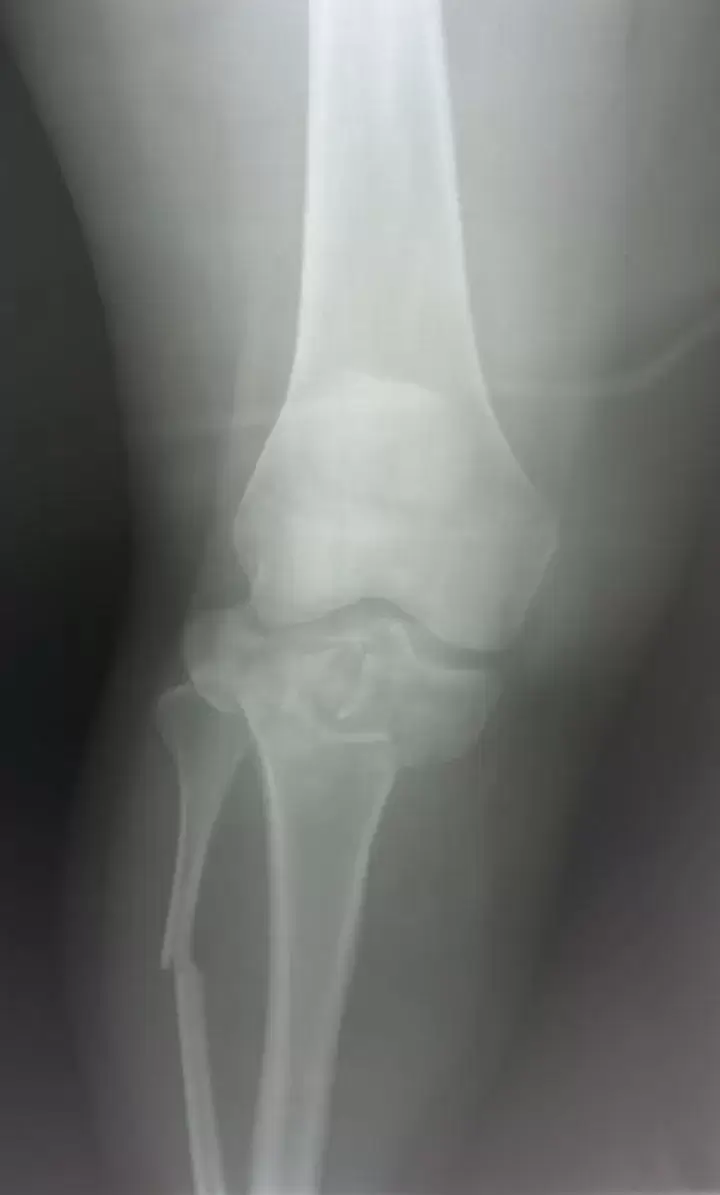

Как сообщает "Вести: Приморье" со ссылкой на Минздрав Приморья, благодаря оперативной и слаженной работе бригады скорой медицинской помощи удалось спасти молодую девушку с крайне тяжёлыми травмами. Пострадавшую экстренно доставили в Спасскую городскую больницу, в травматологическое отделение. Состояние пациентки оценивалось как крайне тяжёлое: травматический шок, открытые переломы костей голени, множественные переломы таза, обширные рваные раны нижних конечностей.

После стабилизации состояния врачи провели сложнейшее оперативное вмешательство — выполнены наружная и внутренняя фиксация переломов таза и голени, лапароскопия для исключения повреждений внутренних органов, а также первичная хирургическая обработка ран. Операция прошла без осложнений», – рассказали специалисты больницы. После этапа реанимации, по согласованию с краевыми медицинскими учреждениями, пациентку перевели в Краевую клиническую больницу №2 для дальнейшей реабилитации.